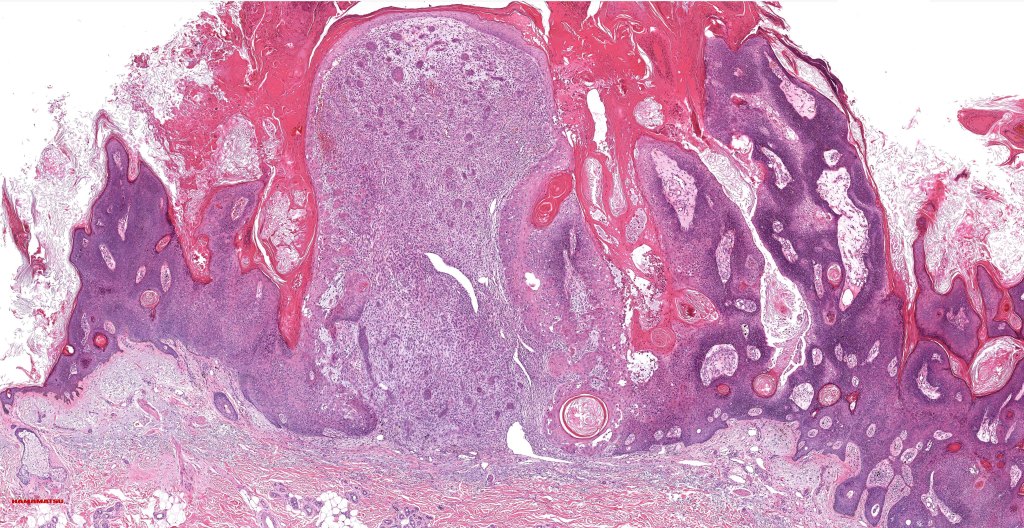

•Biphasic tumor

•Possible epithelial to mesenchymal transition

•Admixture of squamous carcinoma & pleomorphic spindled cell, osteoid, chondroid, MFH-like +/- osteoclast-like giant cells & rarely, smooth muscle, skeletal muscle, myofibroblastic or angiosarcomatous elements

If only the sarcomatous component is present in the biopsy specimen, it will only be when the lesion is fully excised that the correct diagnosis can be made. The main differential diagnosis is metastatic metaplastic squamous cell carcinoma (which can arise at a very wide variatey of sites). Clinicopathological correlation is often essential.